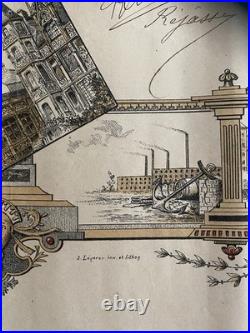

Ecole de Pharmacie de Paris (1836) : Diplôme de pharmacien 1836. La création et l’organisation de l’Ecole de Pharmacie de Paris datent de la loi du 11 avril 1803 et du décret du 8 octobre de la même année. De sa création en 1803. À son rattachement à l’Université en 1840, aucun acte législatif ou règlementaire majeur ne vient modifier la situation de l’école. En 1803 comme en 1836, date de ce document, des professeurs de l’Ecole de Médecine de Paris siègent dans les jurys d’examen. Ceci explique que ce diplôme soit délivré par les «. Professeurs à l’Ecole de Pharmacie de Paris, et Professeurs à l’école de médecine de la même Ville. Pour l’Ecole de Médecine. Médecin et chimiste espagnol, naturalisé français en 1818, il est un pionnier de la toxicologie médico-légale. Il signe ce document deux fois. La première en qualité de professeur, depuis 1819, à la faculté de médecine de Paris. La seconde comme doyen (1831 à 1848) de cette même école. Depuis 1834, il est également membre du Conseil royal de l’Instruction publique. Reçu docteur en médecine en 1820, il devint aide naturaliste au Muséum d’Histoire naturelle en 1827. En 1831, il obtient la place de professeur d’histoire naturelle médicale à la Faculté de Médecine de Paris, reprenant ainsi la fonction de son père, le botaniste Louis Claude Richard (1754 -1821). Pour l’Ecole de Pharmacie. Reçu maître en pharmacie en 1787, il s’adonne ensuite à la chimie. Attaché comme pharmacien à la maison de l’empereur, il accompagne Napoléon Ier lors de ses campagnes en Autriche et en Prusse. Lors de la fondation en 1803 de l’école de pharmacie, il occupe la chaire de chimie. En 1829, il devint directeur-adjoint et en 1832 directeur. C’est à ce poste qu’il signe ce diplôme. Pharmacien et chimiste français. Il fait d’importantes recherches sur les alcaloïdes d’origine végétale et découvre avec Joseph Caventou la quinine et la strychnine. Figure éminente de la pharmacie et de la chimie, ses recherches mettent en évidence plusieurs principes actifs comme la caféine, la narcotine et surtout la codéine. Louis René Le Canu. Il fait notamment paraître plusieurs mémoire sur le sang, sujet qui ne cesse de l’occuper pendant toute la durée de sa carrière. Document su vélin (335 x 216) avec frontispice au coq et « caducée exotique ». Diplôme délivré à Paris le 2 février 1836 et attribué à Joseph Alexandre BLANCHART. Ce dernier, né en 1812 à Péruwelz en BELGIQUE d’un père pharmacien, bénéficie d’une dispense d’âge pour ses examens. Diplôme avec un pli dans le sens de la longueur et trois dans la largeur. Les produits proposés à la vente sont de nature, de poids et de tailles très hétérogènes. Le paiement est considéré comme « soldé » une fois que l’argent envoyé par l’acheteur a été déposé sur le compte du vendeur. Paiement en ligne par carte bancaire. Par virement national ou international.